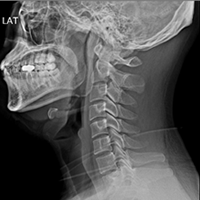

• 정상 경추 X-RAY

완만한 C자 커브

• 일자목 X-RAY

C자 커브 소실

• 거북목 X-RAY

역 C자 커브